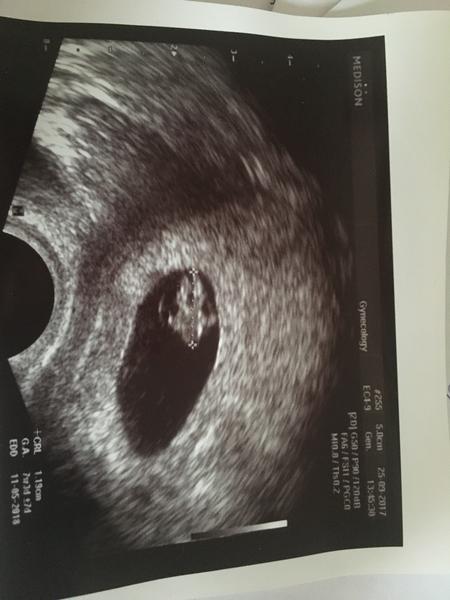

Ahojky holky muzu se k vam pridat? Minuly tyden v patek tj.pred 8dny jsem byla na embryotransferu jedno 5denniho embryjka. Je to nase prvni ivf. Na krev mam jiz az v patek, to je silene cekani...☹ dnes je prvni den kdy bych mela dostat menstruaci.

Ahoj holky, chci se zeptat za jak dlouho po ET jste byli na ultrazvuku? Ja jsem dnes 14den po ET na testu uz krasna dalnice a krev mi brali dneska s tim ze vysledky v pondeli a podle nich ultrazvuk az za 14dni? To se mi zda nejak dlouho?

Tak jo 😉 bojim se aby nebylo mimodelozni proto se divim tech 14dni..to je ale cekani to je des 🙂